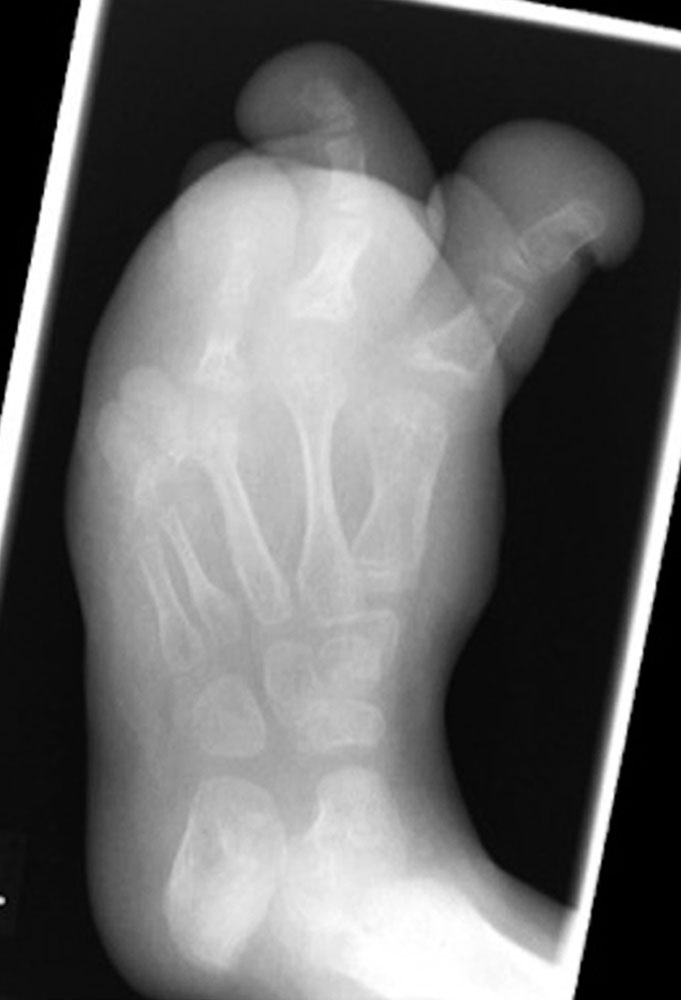

This is a particular diagnostic problem in patients with CLOVES syndrome, where there is often a massive increase in plantar fat.

However, the origin of the leg length discrepancy can be further objectified by examination in the prone position. Here, the length of the lower leg and foot can be compared on both sides.

If, for example, there is no difference in length, but a pelvic obliquity was present during the examination in the standing position, the cause can be attributed to different thigh lengths. Even with this examination, however, it is not possible to reach a conclusion about the pure osseous length of the lower legs if there are foot deformities with or without soft tissue hyperplasia.